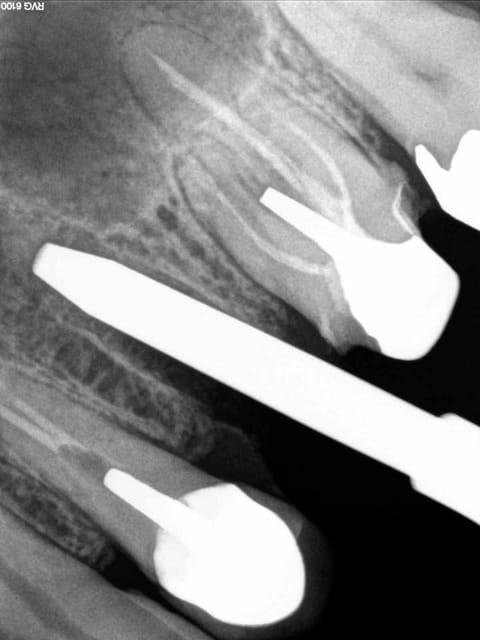

Un confrère : " avec la CCAM, comment il faut coter la radio après pose des faux moignons" ? (10 déc 2014!)

Ben oui, faut savoir que ça existe !!!